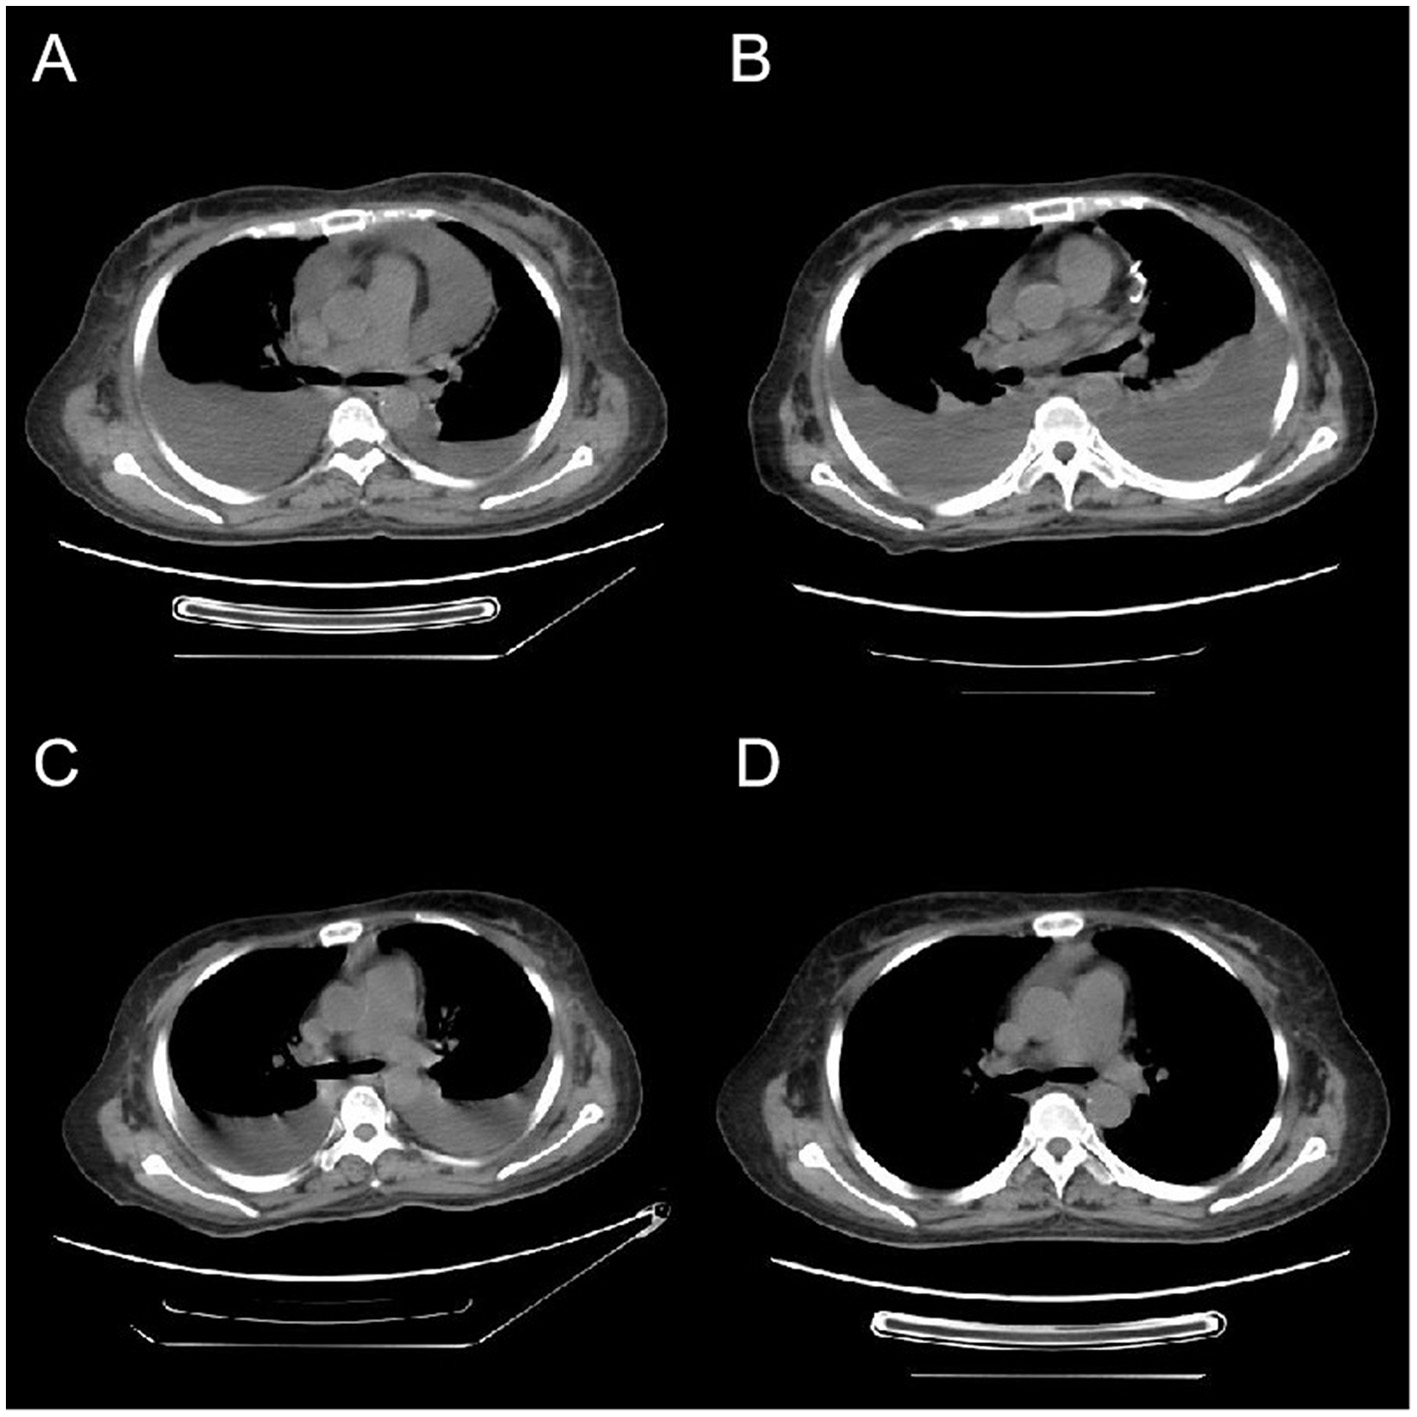

On January 9, 2024, the patient was re-admitted with oliguria and bilateral lower limb edema. Prior to the onset of novel symptoms, the patient had mild chronic GVHD (skin and mouth involvement, scored as 1 each.) and was managed with low-dose methylprednisolone therapy (0.1 mg/kg). Despite occurring during the COVID-19 pandemic, the patient had not received the COVID-19 vaccine or any other vaccinations. Chest (Figure 1) and abdominal CT scans demonstrated bilateral pleural effusion, ascites, and pericardial effusion. The complete blood count revealed a white blood cell count of 8.90 × 109/L, a hemoglobin level of 114 g/L, and a platelet count of 62.00 × 109/L. The B-type natriuretic peptide (BNP) level was 38.20 pg/ml, plasma albumin quantification was 26.50 g/L and thyroid function tests were normal. Urine analysis revealed mild proteinuria, with a 24-h urine protein quantification of only 499 mg. The patient underwent intravenous administration of methylprednisolone (2 mg/kg), ulinastatin, furosemide/torasemide, and sufficient albumin infusions, but the patient did not respond to these therapy. The patient exhibited pronounced abdominal distension, prompting the execution of abdominocentesis for the purpose of draining excess fluid and alleviating symptoms. The analysis of the ascitic fluid indicated a total cell count of 44 × 106/L, with a white blood cell count specifically measuring 4 × 106/L. The total protein concentration in the ascitic fluid was quantified at 5.8 g/L, while adenosine deaminase (ADA) activity was determined to be 1.80 U/L. Additionally, the quantitative analysis of the AML1::ETO fusion gene of the ascitic fluid yielded a negative result. Although asymptomatic for viral infections, the patient underwent viral testing to identify the cause of the novel symptom. The screening for herpesvirus in ascites samples resulted in negative findings. High-throughput sequencing of ascitic fluid pathogens yielded negative results. The quantitative interleukin-6 (IL-6) level in the ascitic fluid was 529.77 pg/ml. The patient received treatment with hydroxyethyl starch (HES) and tocilizumab, however, no significant therapeutic effect was noted. Given the complexity of this case, multiple rounds of internal discussions were held among specialized experts. Although the patient exhibited significant hypoproteinemia and edema, but did not fulfill the diagnostic criteria for nephrotic syndrome, but the professors participating in the discussions concluded that certain diseases, notably nephrotic syndrome, could not be definitively excluded. Following the patient's inadequate response to glucocorticoid therapy, the professors recommended initiating treatment with rituximab and intravenous immunoglobulin after thorough discussion. The patient, however, remained unresponsive to the treatment. Based on a comprehensive assessment of the patient's clinical symptoms, laboratory results, and imaging findings, a diagnosis of late onset CLS was confirmed in accordance with the established criteria in the literature (3).

Figure 1. Variations in CT imaging throughout the patient's treatment regimen. (A) The initial CT scan upon admission, revealing the presence of bilateral pleural effusions and a pericardial effusion. Four weeks post-admission, (B) a CT scan that exhibits an augmentation in pleural effusions from baseline, along with the presence of a visible pericardial drainage catheter. (C) A CT scan conducted 3 days following bevacizumab administration, demonstrating a notable decrease in pleural effusions. One week subsequent to the completion of bevacizumab therapy, (D) a CT scan indicating the full resolution of pleural effusions.

The patient exhibited a poor response to all the aforementioned treatments characterized by rapid weight gain, worsening abdominal distension, overt hypotension, tachycardia, and dyspnea. The plasma albumin concentration has diminished to 19 g/L, accompanied by a notable elevation in plasmatic creatinine levels. CT and ultrasound examinations revealed a substantial elevation in pleural, ascitic, and pericardial effusions, the patient underwent thoracentesis and pericardiocentesis procedures aimed at alleviating symptoms related to compression. Considering the patient's critical state and non-responsiveness to other therapies, coupled with the documented success of bevacizumab in treating CLS (2), we initiated a therapeutic regimen involving bevacizumab. The off-label utilization of bevacizumab has been authorized by the Pharmaceutical Affairs Committee of Beijing Lu Daopei Hospital. Separate written informed consent was obtained from the patient before the study, in accordance with the Declaration of Helsinki, and permission to publish the results was granted after the study. This retrospective study was approved by the Ethics Committee of Beijing Lu Daopei Hospital. Bevacizumab (5 mg/kg) was administered intravenously over a 90-min period, to prevent venous thrombosis, the patient underwent subcutaneous injections of enoxaparin. Following treatment, the patient exhibited notable improvement in symptoms, marked by decreased abdominal distension, enhanced urine output, and a substantial reduction in pleural and pericardial effusion drainage. The plasma albumin concentration escalated to 27.5 g/L (Figure 2). A subsequent CT scan, conducted 3 days post-treatment, revealed a pronounced decline in pleural effusion. Subsequently, the patient underwent bevacizumab therapy at a biweekly interval for four cycles, ultimately leading to the complete resolution of pleural effusion. Notably, the patient's pretreatment plasma VEGF level was within normal range (7.9 pg/ml; <142 pg/ml), aligning with previous literature reports (2). During the treatment, the patient's cGVHD in the mouth showed improvement, while stabilization was observed in skin cGVHD. Following the treatment, the patient's clinical symptoms of discomfort resolved, resulting in a high level of satisfaction with the treatment's efficacy.